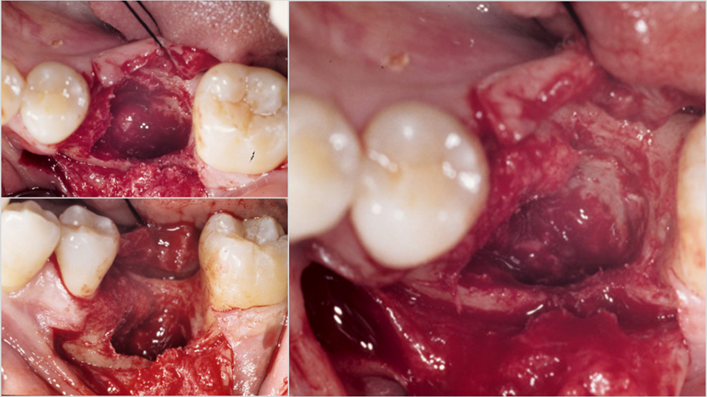

Clinical case: Single molar implant with bone augmentation

- Courtesy of Dr. Jung Sam Lee, Korea -

Keywords

AnyOne, bone augmentation, osteotomy socket, peri-implant tissue, autogenous bone, GBR, single replacement, Auto-Max, Dr. Jung Sam Lee

Products:

AnyOne implant system, Auto-Max